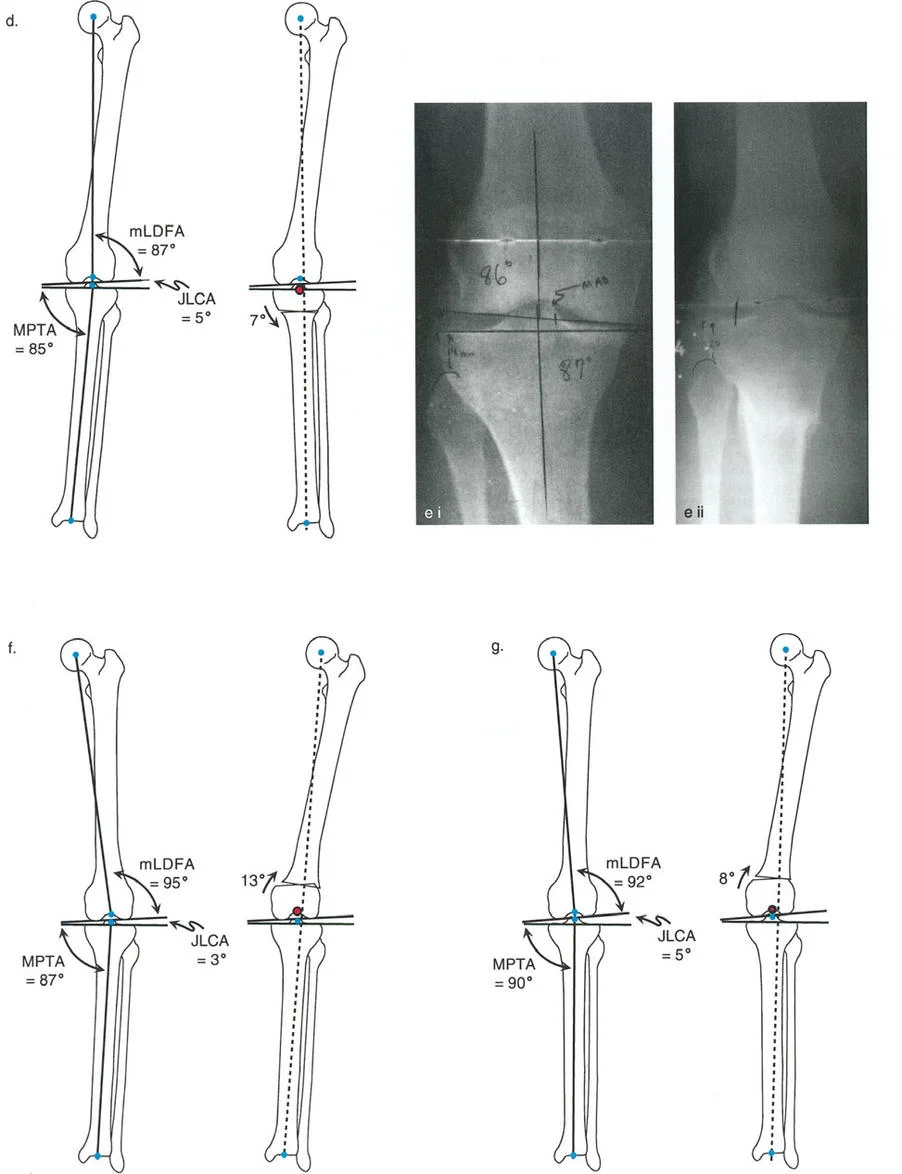

- تحديد مصدر الخلل في المحاذاة (باستخدام MAT):

- يستخدم الدكتور هطيف تحليل المحاذاة الميكانيكية الشامل (MAT) لتحديد ما إذا كان التشوه في عظم الفخذ أو الظنبوب أو كليهما.

- متى يتم قطع عظم الظنبوب؟ عندما يكون التشوه في الظنبوب بشكل واضح (MPTA <85 درجة) وعظم الفخذ طبيعيًا.

- متى يتم قطع عظم الفخذ؟ عندما يكون التشوه في عظم الفخذ بشكل واضح (mLDFA >93 درجة) وعظم الظنبوب طبيعيًا.

- التشوه المشترك: في بعض الحالات، قد يكون التشوه موجودًا في كل من عظم الفخذ والظنبوب، ويتطلب الأمر إجراء قطع عظم في كليهما.

- تنبيه سريري: يُعد الجمع بين عظم فخذ روحي (valgus) وعظم ظنبوب متقوس (varus) مزيجًا سيئًا يؤدي إلى تدهور مفصل الركبة. يحرص الدكتور هطيف على تصحيح كلا التشوهين في هذه الحالات.